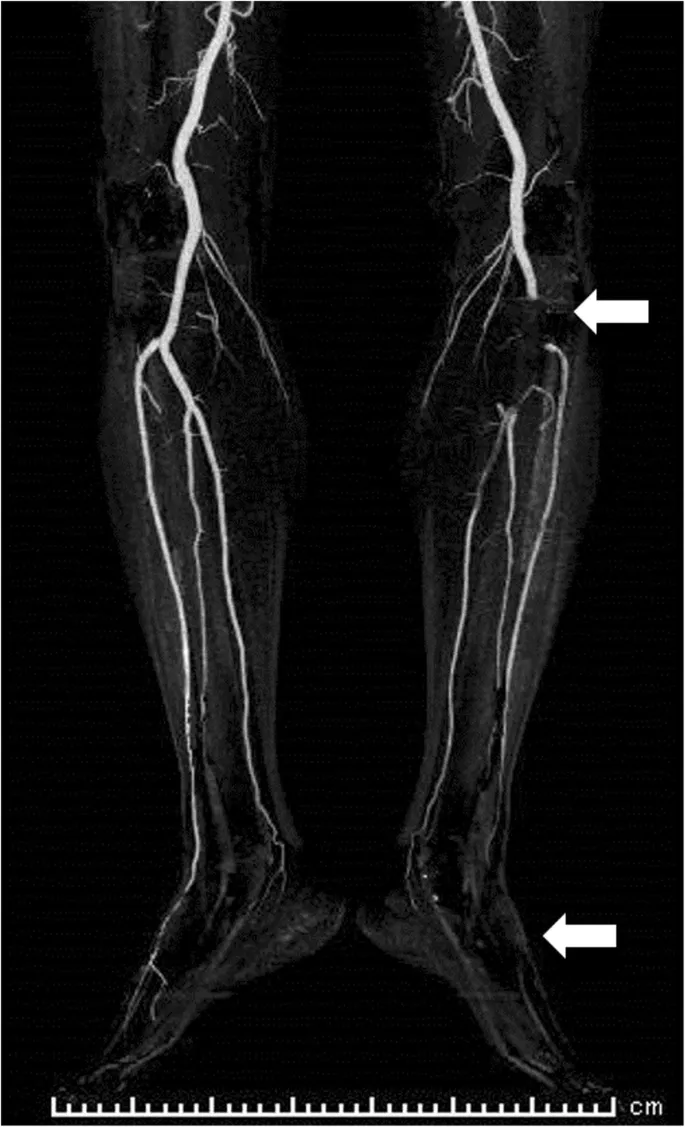

- Bedside Doppler: Confirms absent arterial flow.

- CT Angiography (CTA): Gold standard. Rapidly identifies the location and extent of the occlusion ("the stop sign").